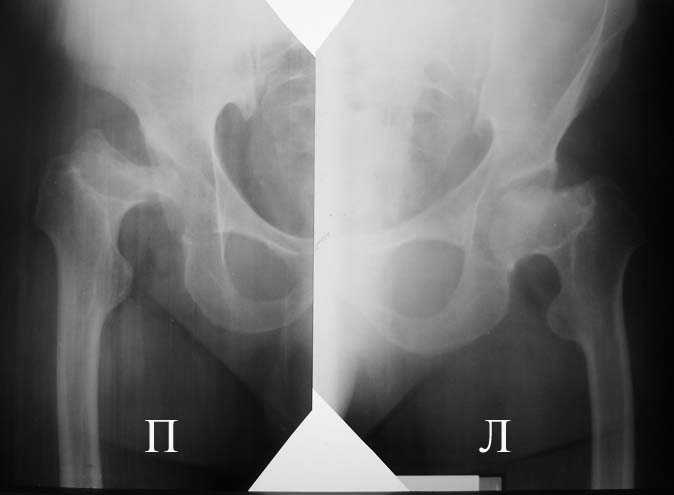

Аксиальная проэкция обоих т/б суставов